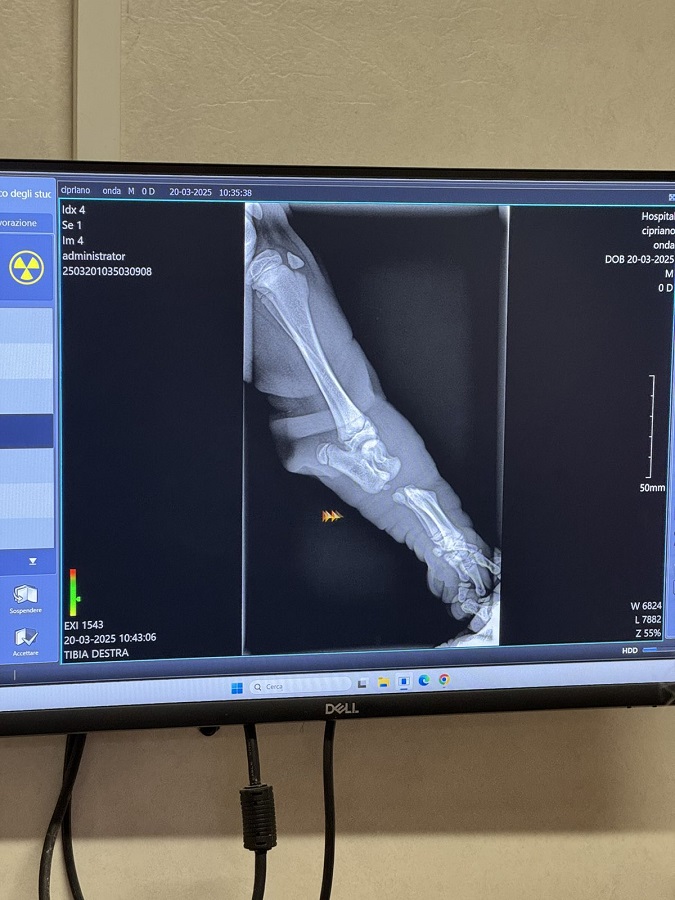

У період з 10 березня до 06 червня 2025 року здобувачка вищої освіти факультету ветеринарної медицини Орина ЛИФАР пройшла стажування у ветеринарній клініці італійського університету. Вона працювала у відділеннях терапії та хірургії ветеринарній клініці, де отримала глибокі практичні знання та навички. Цей період став для учасниці академічної мобільності неоціненним у плані професійного розвитку, надавши змогу попрацювати пліч-о-пліч з провідними ветеринарами, застосовуючи сучасні підходи до діагностики та лікування тварин. Зокрема, у хірургічному відділенні Орина ЛИФАР виконувала обов’язки асистента хірурга: готувала пацієнтів до операцій, підтримувала стерильність інструментів, брала участь у хірургічних втручаннях і забезпечувала післяопераційний догляд. Крім того, представниця нашого університету вела медичну документацію, брала участь в організації лікувального процесу та контролювала виконання призначень. Такий комплексний підхід дозволив Орині ЛИФАР краще осягнути специфіку клінічного ведення пацієнтів.